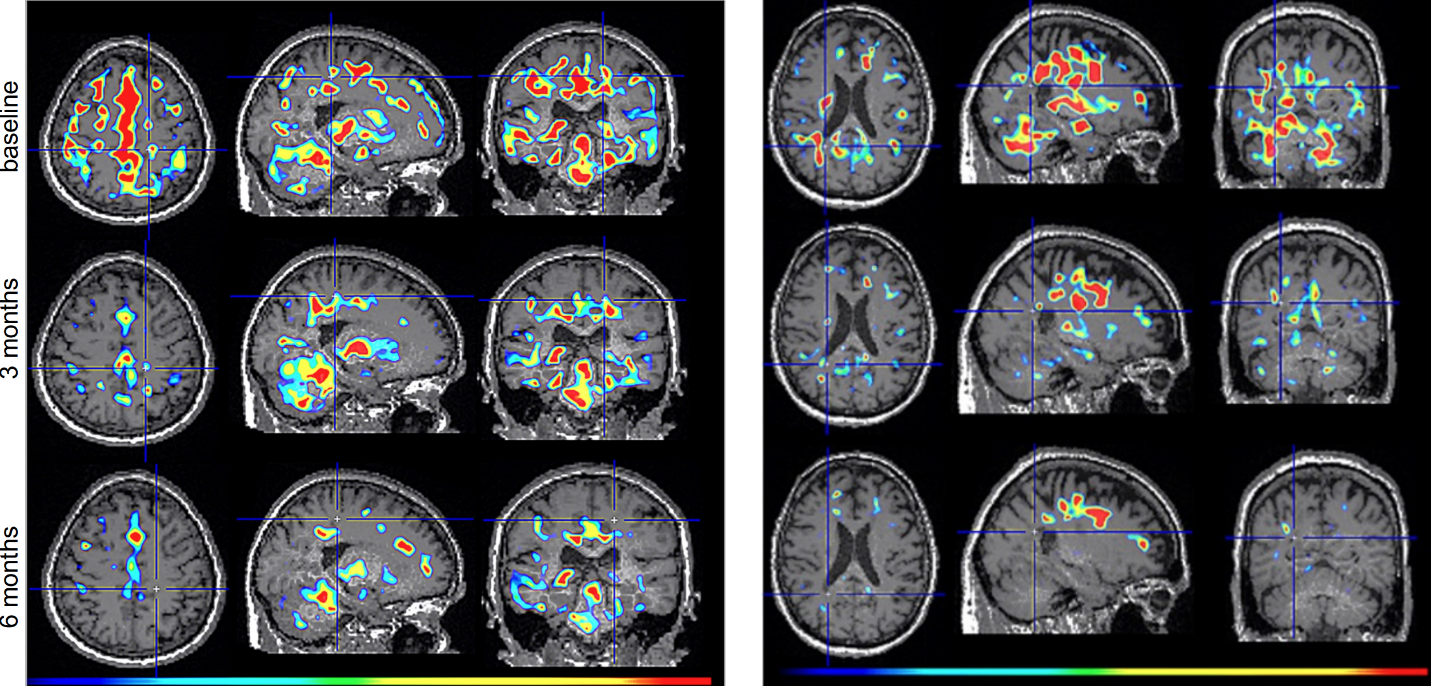

Figure 2. TSPO-PET scans from intranasal foralumab-treated MS patients showing marked reduction in microglial activation over a 6-month treatment period.

Foralumab, a fully human anti-CD3 monoclonal antibody, is a biological drug candidate that has been shown to stimulate T regulatory cells when dosed intranasally. At present, 14 patients with Non-Active Secondary Progressive Multiple Sclerosis (na-SPMS) have been dosed in an open-label intermediate sized Expanded Access (EA) Program (NCT06802328) with either an improvement or stability of disease seen within 6 months in all patients. In addition, intranasal foralumab is currently being studied in a Phase 2a, randomized, double-blind, placebo-controlled, multicenter, dose-ranging trial in patients with non-active secondary progressive multiple sclerosis (NCT06292923).

Figure 2

TSPO-PET scans from intranasal foralumab-treated MS patients showing marked reduction in microglial activation over a 6-month treatment period.